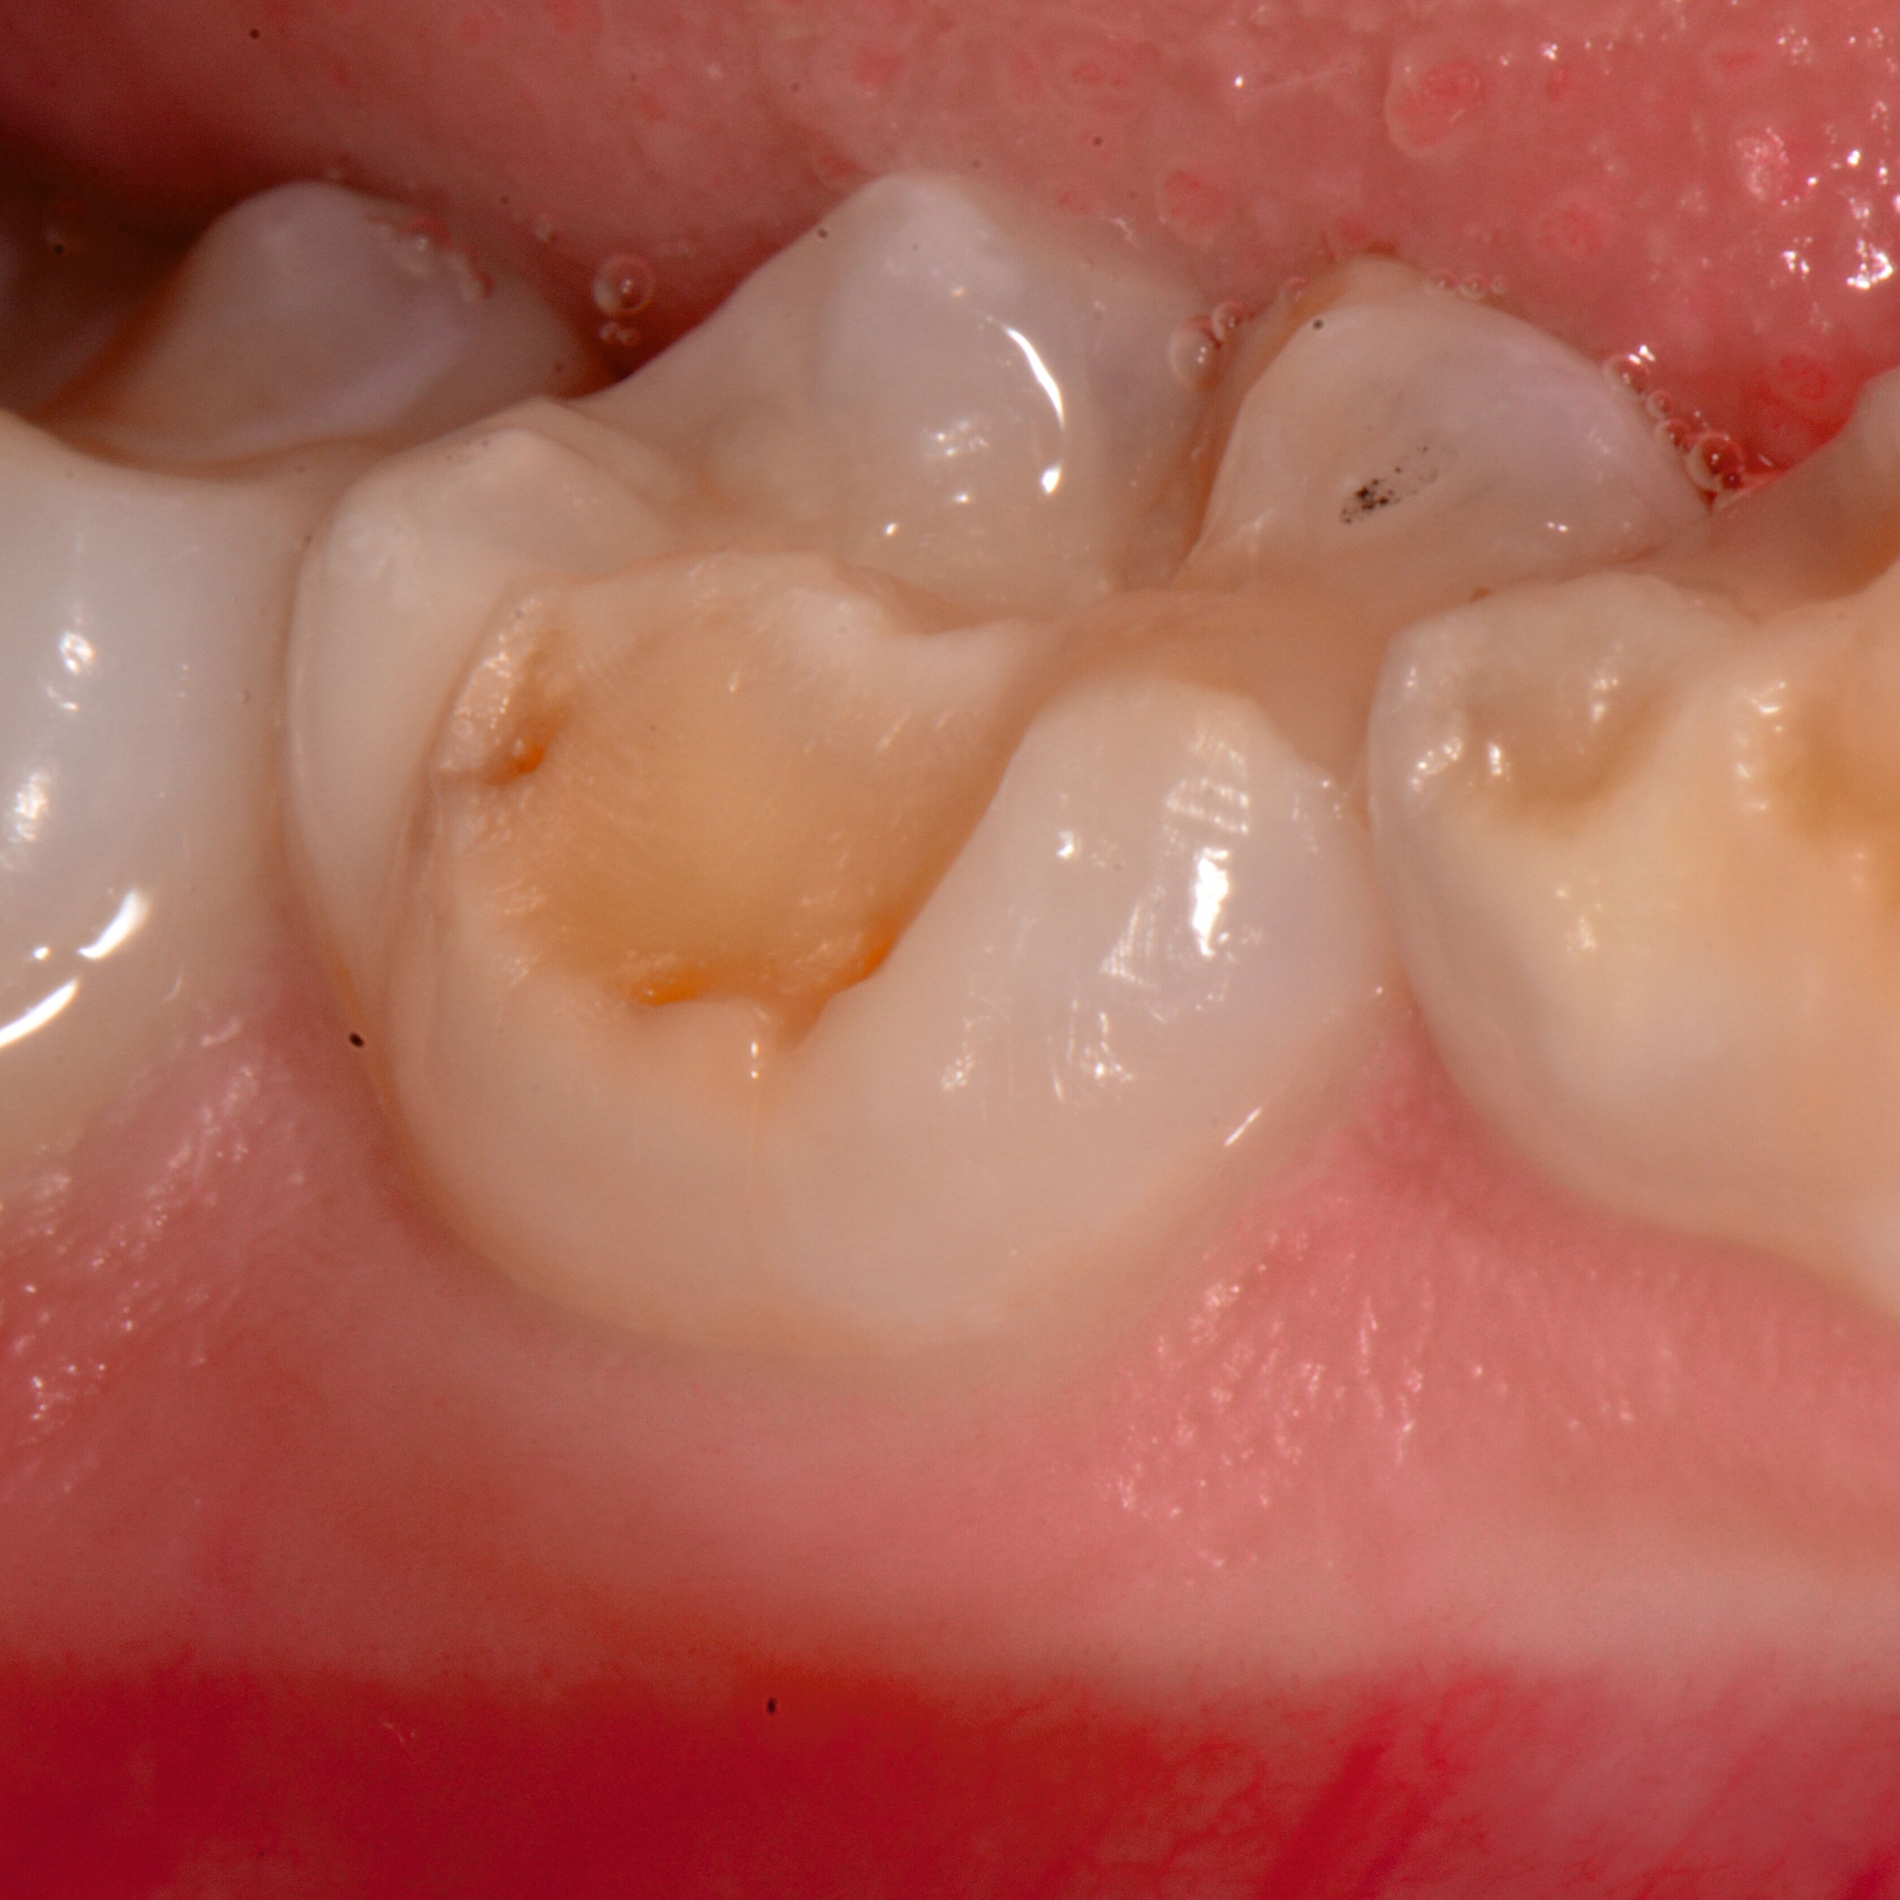

Das klinische Erscheinungsbild an bleibenden Zähnen zeigt typischerweise weißlich-gelbe bis gelblich-braune Opazitäten, die zumindest in einigen Bereichen durch eine scharfe Abgrenzung (engl.:„demarcated opacities“) zum gesunden Zahnschmelz charakterisiert sind (Abbildungen 3 und 4). Die abgegrenzten Hypomineralisationen befinden sich mehrheitlich im Bereich der inzisalen Kronenhälfte unabhängig von dem Auftreten an Front- oder Seitenzähnen. Die Ausprägung am Zahn kann dabei auf einzelne Areale oder Höcker begrenzt sein.

Für die Dokumentation und Klassifikation der MIH wurden verschiedene Systeme vorgeschlagen. Als historisch und veraltet gilt der (modifizierte) DDE-Index. Demgegenüber haben die Kriterien der EAPD – abgegrenzte Opazitäten (Abbildung 3 und 4), Schmelzeinbrüche (Abbildung 5), atypische Restaurationen (Abbildung 6) – mittlerweile die weiteste Verbreitung gefunden. Diese wurden 2003 erstmals zur Beschreibung der MIH auf empirischer Basis publiziert [Weerheijm et al., 2003] und den Jahren 2010 und 2022 im Rahmen der damaligen MIH-Workshops bestätigt [Lygidakis et al., 2010; 2022].